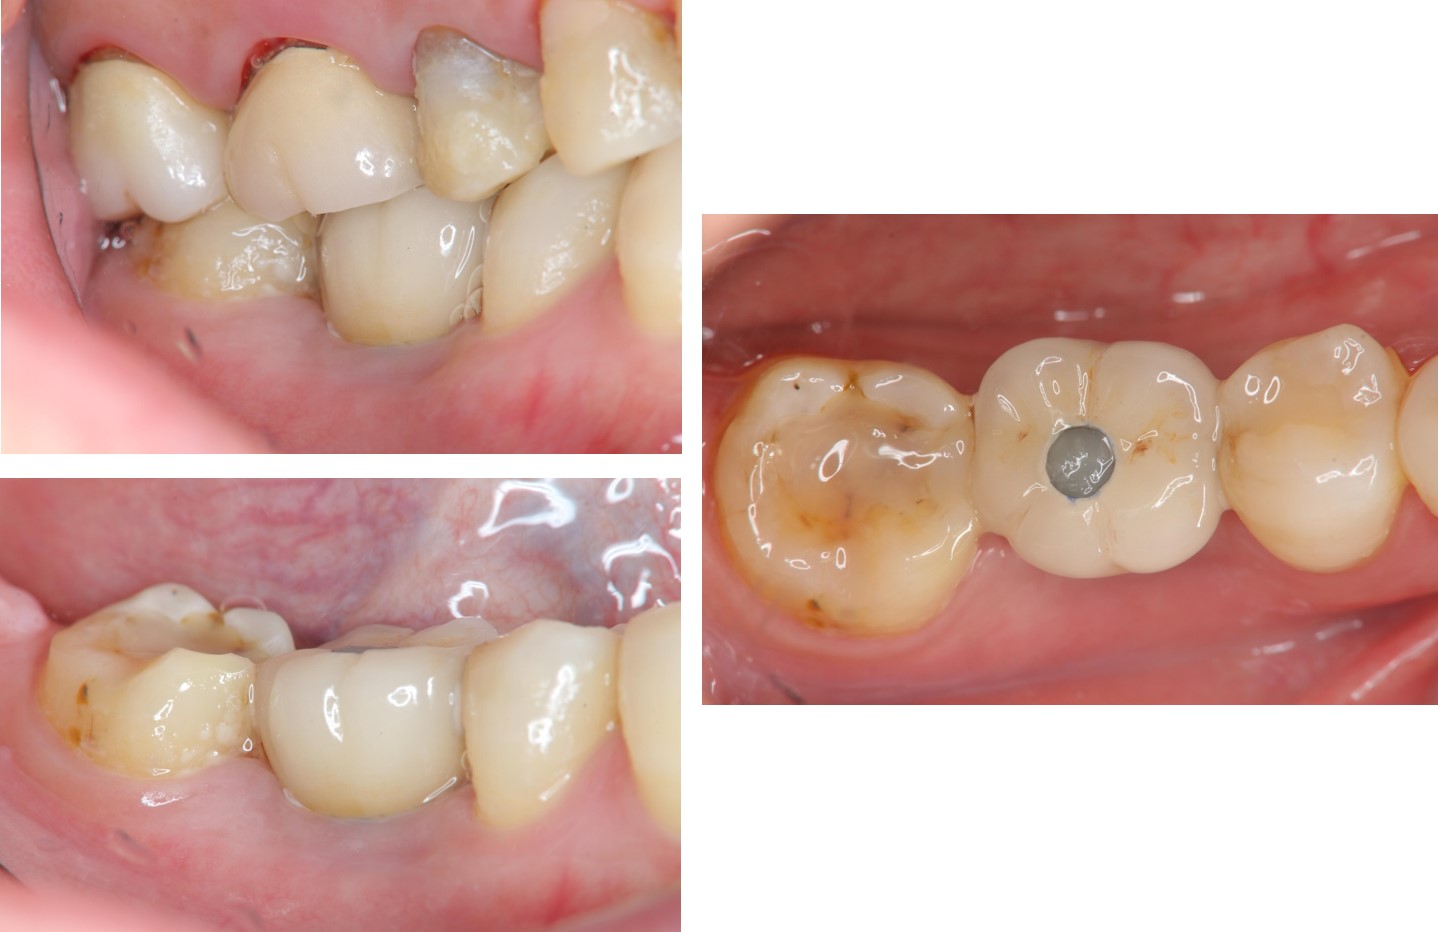

面弓轉移,上咬合器

咬合器上製作瓷牙

治療後,咬合牙周適應良好

治療後,密合度良好

術前、術後比較

使用單顆植牙,不需修磨正常的牙齒,清潔更方便,且咬合更強。